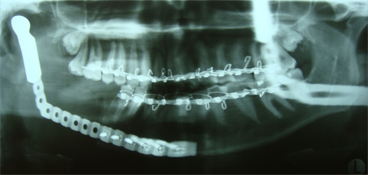

Après avoir longuement discuté avec la patiente, il a été décidé de procéder à une résection de la portion atteinte du maxillaire inférieur. L'intervention a consisté en la résection de l'os sclérotique, y compris du condyle, de la branche montante et d'une portion du corps du maxillaire inférieur droit. Les dents 45, 46 et 47 ont aussi été incluses dans la résection, laquelle a été prolongée jusqu'à ce qu'on atteigne la moelle osseuse saine – signe d'un tissu osseux sain. La reconstruction provisoire a consisté en la mise en place d'une plaque de reconstruction portante sur laquelle a été fixée une tête de condyle prothétique (ill. 3). La patiente s'est très bien rétablie après l'intervention et tous les symptômes associés à l'infection ont rapidement disparu (ill. 4). Après la résection, l'antibiothérapie a été poursuivie pendant 3 mois, moment auquel tous les symptômes de l'ostéomyélite avaient disparu.

Ill. 3 : Radiographie panoramique du maxillaire inférieur droit réséqué et de la plaque de reconstruction portante avec tête de condyle prothétique.